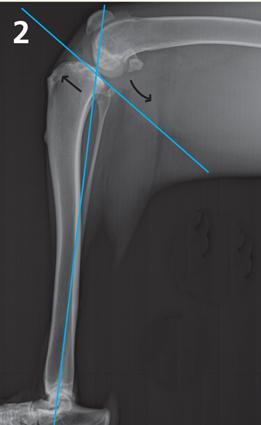

The bone just below the knee or stifle joint is the tibia and the bone above is the femur. The top of the tibia is the tibial plateau. All dogs have a sloping tibial plateau.

During weight bearing, the femur slides down the tibial plateau. The (ACL) stops this downward slope, therefore, is under constant tension during weight bearing. It is this biomechanical problem that leads to most ACL ruptures and may cause older repair techniques to fail.

The TPLO involves an osteotomy to reorient the tibial plateau to a near level platform. This provides a biomechanically stable joint. The new tibial plateau angle also reorients the posterior cruciate ligament (PCL), enabling it to function as both the ACL and PCL.